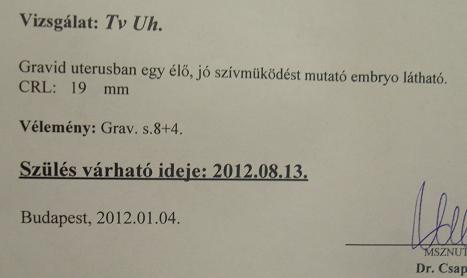

Megmutatom az uhu képeket, szinte törvényszerű volt, hogy ma nem kapunk, de nem gond, láttuk!!!!

majd a mostani uhu-n már 19mm!! jó nagyot nőtt! és hallottam a szívhangot!!! megmutatta a doki, lányok zsebkendő-hiányban szenvedtem utána elég sokáig! szóval most már olyan babóca formája van, sajnálom, hogy nem kaptam képet, viszont kaptam egy ilyet, és a terhesség kora 8hét+4 nap, azaz mégiscsak a bikácsi szülcsinapozó hétvége a ludas...

Ja és Csapó doki nem lesz nyáron amikorra kiírtak így ajánlott maga helyett egy doktornőt, kedves, aranyos, fura, hogy nő, de legyen. Főleg, hogy Csapó ajánlotta.